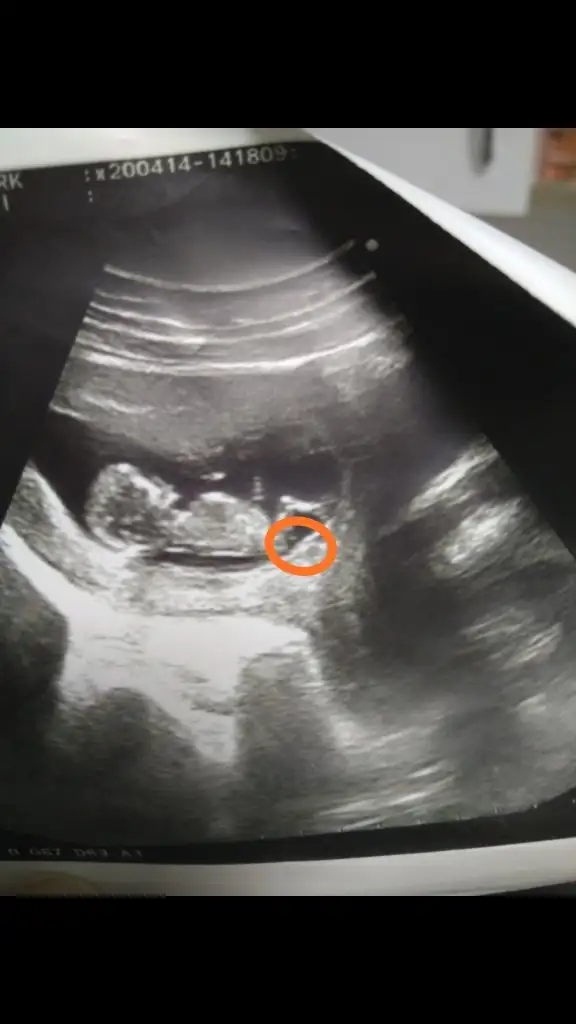

Sevgili arkadaşlar kaç gündür fotoğrafa filozof edasıyla bakıyorum resmen 😊 size de danışmak istedim yeniden, bu nub denilen çıkıntılı acaba benim ufaklikta daire içerisine aldığım çıkıntı mıdır? Eğer o kısım ise bu teoriye göre gerçekten kıza benziyor bizimkisi 🤗

• IMG_20200424_212411.webp

IMG_20200424_212411.webp

15,6 KB · Görüntüleme: 83

İşte tam görünmüyor o nedenle emin değilim başka usg de paylaşın yazmıştım sanırım 😊